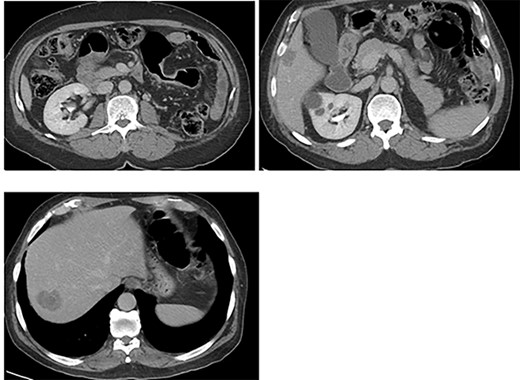

An otherwise healthy 73-year-old male, presented with rectal bleeding 6 months back. Colonoscopy revealed a sigmoid colon mass about 25 cm from the anal verge extending 10 cm proximally and a biopsy confirmed invasive adenocarcinoma (Fig. 1) Computed tomography of the abdomen and pelvis revealed a circumferential wall thickening involving the distal colon/proximal sigmoid colon spanning for 6 cm with maximum thickness of 2.3 cm, and it was also associated with surrounding fat stranding and multiple regional lymph nodes. Liver lesions were described as ill-defined hypodense lesions in two segments. The first lesion was seen in segment 7 measuring 6 × 7.5 cm and the other was seen in segment 5 measuring 6 × 3 cm (Fig. 2). Furthermore, chest CT showed no lung metastasis and a carcinoembryonic antigen level of 24.8. Eventually, a diagnosis of metastatic sigmoid adenocarcinoma with liver lesions was made. The multidisciplinary team decided to start the patient on Nac and then the case was reassessed for further resection. After completing five cycles FOLFOX, a CT of chest, abdomen and pelvis was performed for evaluating the response. The primary descending colon tumor demonstrated reduction in bulk with persistent serosal irregularity and no definitive regional lymphadenopathy was detected. The hepatic lesions revealed a partial response; in segment 7, the lesion is currently measuring 3.9 cm and in segment 5, the lesion measures 2.7 cm. Partial response to therapy was noted by a 41% reduction in sum tumor burden as per RECIST criteria (Fig. 3). The clinical tumor node metastasis classification post chemo was calculated to be T2N0M1 for descending colon cancer along with a CEA of <1.7. Despite not adding a biological agent with the systemic therapy which is the standard protocol in metastatic CRC, the patient achieved a remarkable reduction in tumor burden. The patient underwent a laparotomy with a low anterior resection of the rectum and anastomosis, synchronous resection of segments 6 and 8 of the liver along with a right-sided diaphragmatic stripping.

The patient was clinically and vitally stable post operation and was recovering well upon discharge. Pathology revealed no residual tumor, extensive necrosis and calcification with no viable cancer cells with a complete response and a score of 0. Moreover, the sigmoid colon specimen revealed no viable cancer cells, complete response, a score of 0 and nine lymph nodes were found to be negative to malignancy (0/9) (Fig. 4).